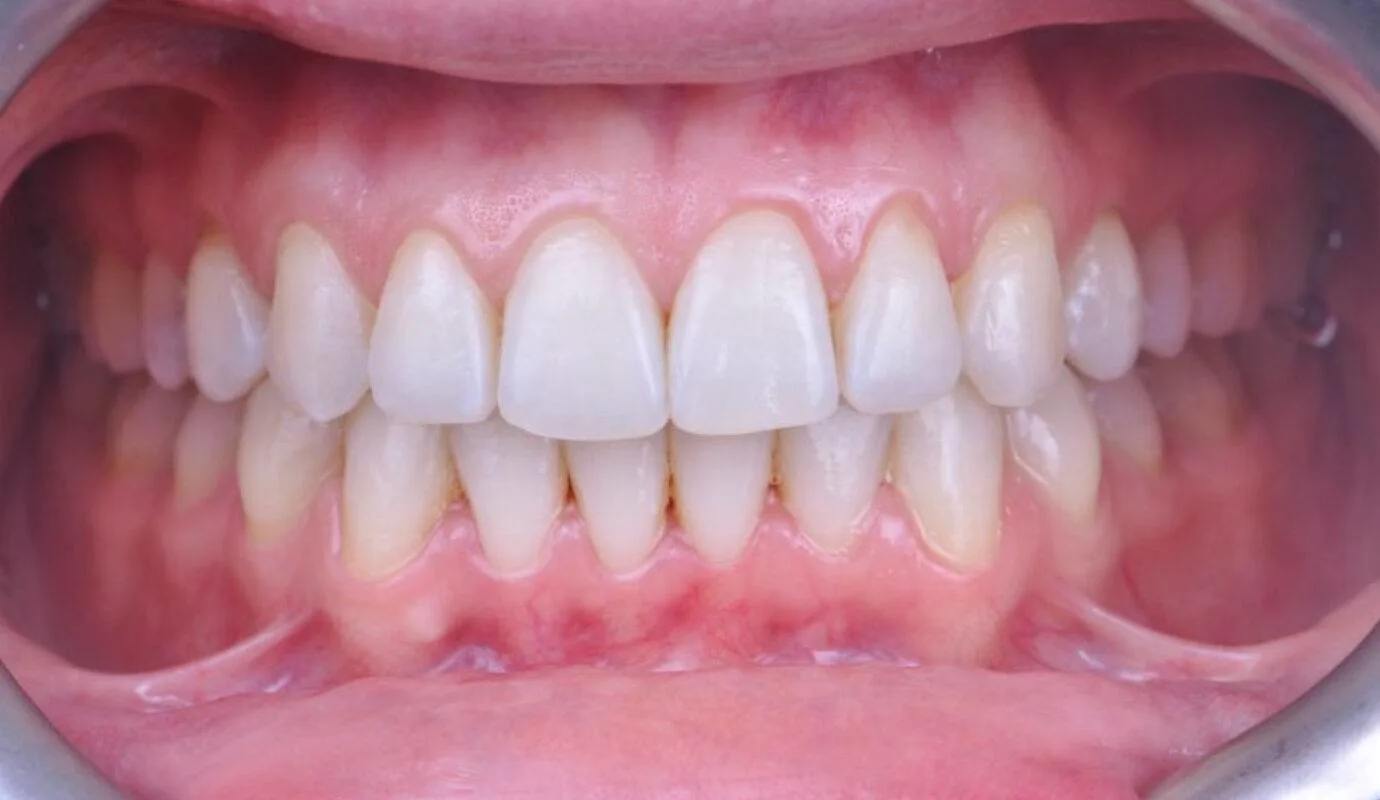

Before & After Invisalign® Gallery